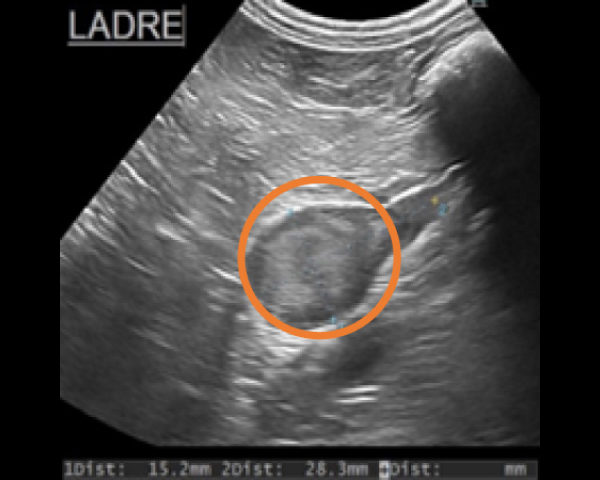

超音波にて副腎腫瘤を確認